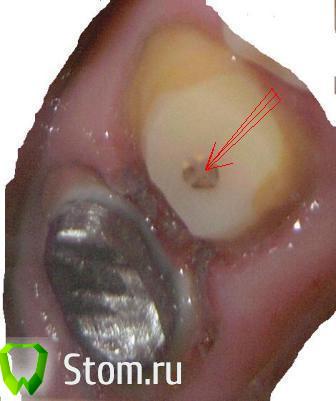

mur-in-law Опубликовано 1 марта, 2012 Автор Поделиться Опубликовано 1 марта, 2012 (изменено) где, что и сколько простоит - сказать невозможно.Спасибо, конечно, но как-то ни о чем...Вот результат сегодняшнего посещения.Обточили. как я понял не только шестерку, но и семерку подправили.Интересно, а что это в центре (указано стрелкой), гуттаперча?Коронки попросил сделать раздельные. Изменено 1 марта, 2012 пользователем mur-in-law Ссылка на комментарий

Dr.Ru Опубликовано 1 марта, 2012 Поделиться Опубликовано 1 марта, 2012 Спасибо, конечно, но как-то ни о чем...чтобы было "о чем" спросите Вашего лечащего доктора.в центре это анкерный штифт Ссылка на комментарий